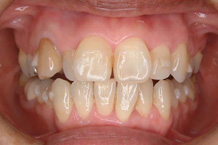

2か月後です。反対咬合は治っています。現在は正常な噛み合せになりました。

これからまだ永久歯に生え替わるので、注意深く定期的に観察していきます。生え替わった後に、また反対咬合になりこともあります。